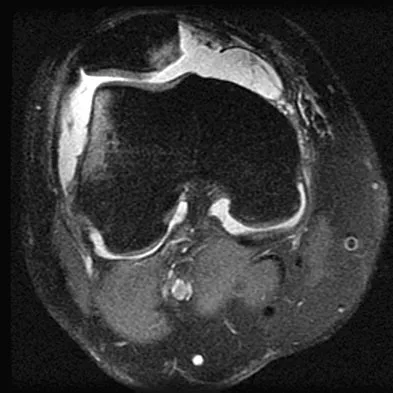

Question 100

Figure 41 shows the MRI scan of a 38-year-old weightlifter. What does the arrow on the MRI scan indicate?

Explanation